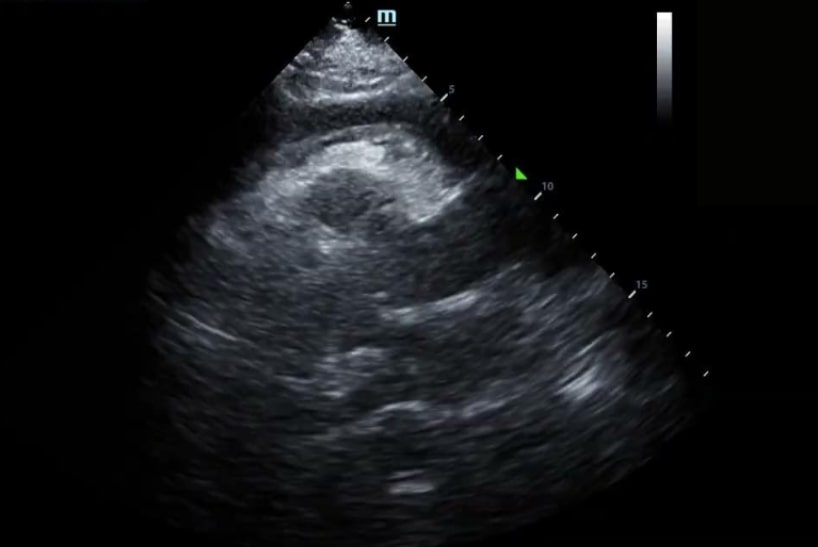

When asked to lie flat for the cardiac exam, he noted worsening chest discomfort. Upon obtaining the initial Parasternal Long Axis (PLAX) view, all eyes in the room grew wide in surprise.

Here you can see a significant pericardial effusion in PLAX and Subxiphoid views with concerns for early tamponade. This was communicated with the cardiology team who promptly drained 400cc of serosanguinous fluid. Ultimately there was no obvious source for this effusion. Since this experience, I always make sure to take at least a quick peek at the heart in respiratory cases where lung ultrasound is unrevealing.